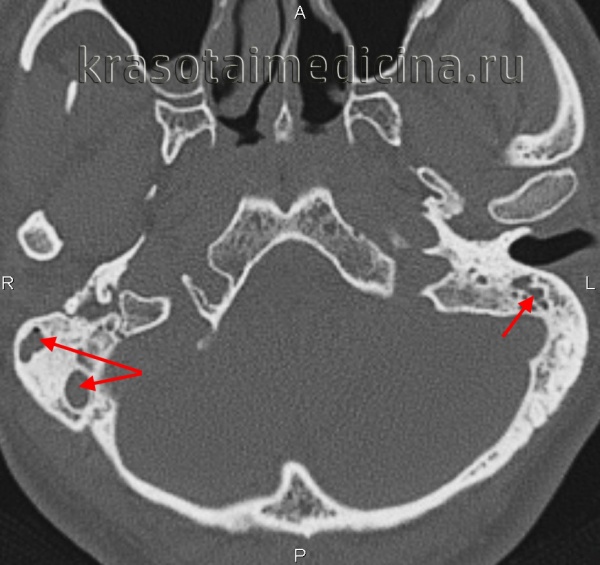

(Слева) При аксиальной КТ в костном окне визуализируется нормальный короткий отросток наковальни справа и головка молоточка. Обратите внимание на хорошо пневматизированный сосцевидный отросток.

(Справа) При аксиальной КТ левой височной кости у пациента с хроническим средним отитом в анамнезе определяется деоссификация короткого отростка наковальни слева. Головка молоточка по размерам и плотности не изменена. Пневматизация сосцевидного отростка снижена вследствие отомастоидита во время его формирования.